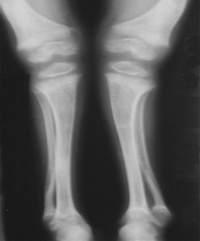

③四肢:“手镯”及“脚镯”;开始行走后,(“O”型)或(“X”型)腿,长骨可发生青枝骨折。

本病主要是引起婴儿抬头、坐、站、行走都较晚。关节松弛而有过伸现象,大脑皮层功能异常条件反射形成缓慢,语言发育落后,贫血等症状。 在一些比较严重的佝偻病的患儿中,还会出现其他的骨骼变形,如鸡胸、漏斗胸、X型腿、O型腿、肋串珠、手镯和脚镯等。

2、中度:可见典型的串珠、手镯、肋软骨沟、轻度或中度的鸡胸、漏斗胸、O或X型腿,也可有囱门晚闭、出牙迟缓等明显的改变。

3、重度:可见明显的肋软骨沟、鸡胸、漏斗胸、脊柱畸型、O或X型腿、病理性骨折等严重改变。

4、后遗症:多见于3岁以后的小儿。经治疗或自然恢复,症状消失,骨骼改变不再进展。X线及血生化检查正常,仅留有不同程度的骨骼畸形。